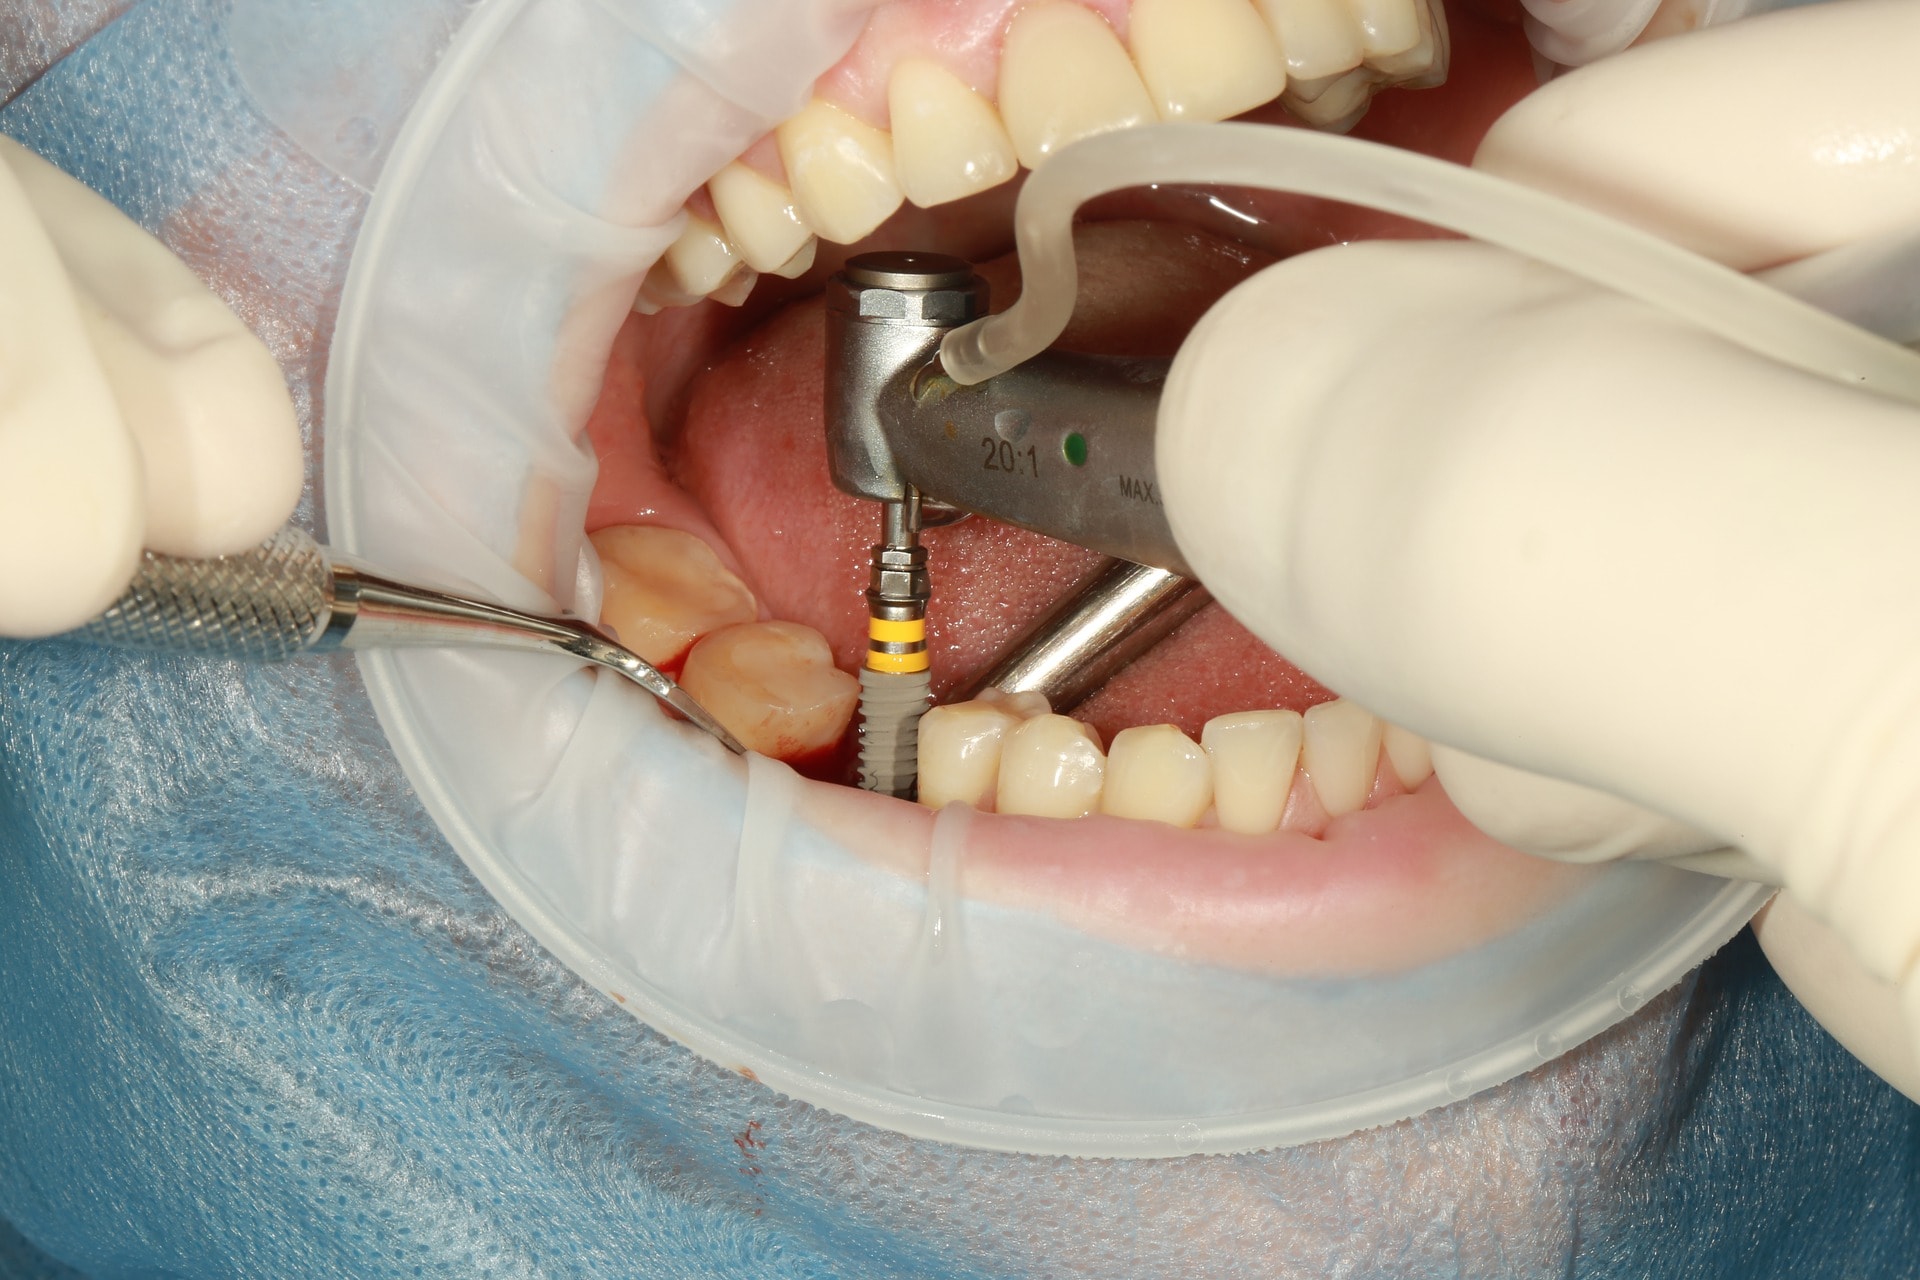

Fogszabályozási miniimplantátum

A modern fogszabályozó kezelések alappillérei a fogszabályozási miniimplantátumok. Óriási előnyökkel jár használatuk, és a kezelések sikerességét hihetetlen mértékben megnövelik. Miniimplantátumok segítségével a korábban csak műtéttel, foghúzással kezelhető pácienseket egyszerű fogszabályozással is tökéletesen kezelni tudjuk! Az önligírozó fogszabályozó rendszerek és miniimplantátumok kombinált használata talán a legsikeresebb technikát jelenti jelenleg. Nagyon minimális helyi érzéstelenítésben történik behelyezésük, mely nagyjából 20-40 másodpercet vesz igénybe! Az injekciót leszámítva teljesen fájdalommentes beavatkozás! A fogszabályozási miniimplantátumok a fogászati implantátumokkal szemben nem kerülnek szoros kapcsolatba a környező szövetekkel, ezáltal későbbi eltávolításuk igazán egyszerű, érzéstelenítő sem szükséges hozzá. Technika- és szájhigiéné érzékeny rendszerről beszélünk. Nem megfelelő fogmosás következményeként a minicsavarok meglazulhatnak, kieshetnek.

Behelyezési területük szerint három fő csoportot különböztetünk meg:

1. A gyökerek közé helyezett miniimplantátumok

Ezeket a miniimplantátumokat a fogak gyökerére merőlegesen helyezzük be, a gyökerek közé. Pontos helyzetüket előzetes kisröntgen alapján határozzuk meg. Ezekkel végezzük a foghiányok zárását, bizonyos fogak pozícióban tartását, elülső fogak felfelé/lefelé mozgatását stb.

2. A gyökereken kívül helyezett miniimplantátumok

Egyre népszerűbb technika, melynek során a minicsavarokat vagy a felső őrlőfogak melletti csonttaréjba (crista infrazygomatica), vagy az alsó őrlőfogak melletti csonttaréjba tekerjük. Előnye, hogy a foggyökereken kívüli területen rögzül a csavar, így nem akadályozza a fogak mozgatását. Segítségével teljes alsó/felső fogív előre/hátra mozgatás is végezhető.

3. A szájpadba helyezett miniimplantátumok (szintén a gyökereken kívül)

Nagy sikerrel alkalmazott, biztos, kiváló csontminőségű behelyezési terület a szájpad. A szájpad középvonalába, vagy enyhén mellé helyezzük be a minicsavarokat, amikkel a felső fogív hátra/előrevitele, és felfelé mozgatása is sikerrel végezhető. Nem kell tehát félni a miniimplantátumoktól, minden esetben nagymértékben segíthetnek minket a tökéletes végeredmény elérésében. Sikerességi rátájuk 95% körül mozog! Akkor is ismertetem használatukat, ha nem biztos, hogy szükség lesz rájuk, hiszen biztosra megyünk és tökéletes mosolyt és harapást szeretnénk.